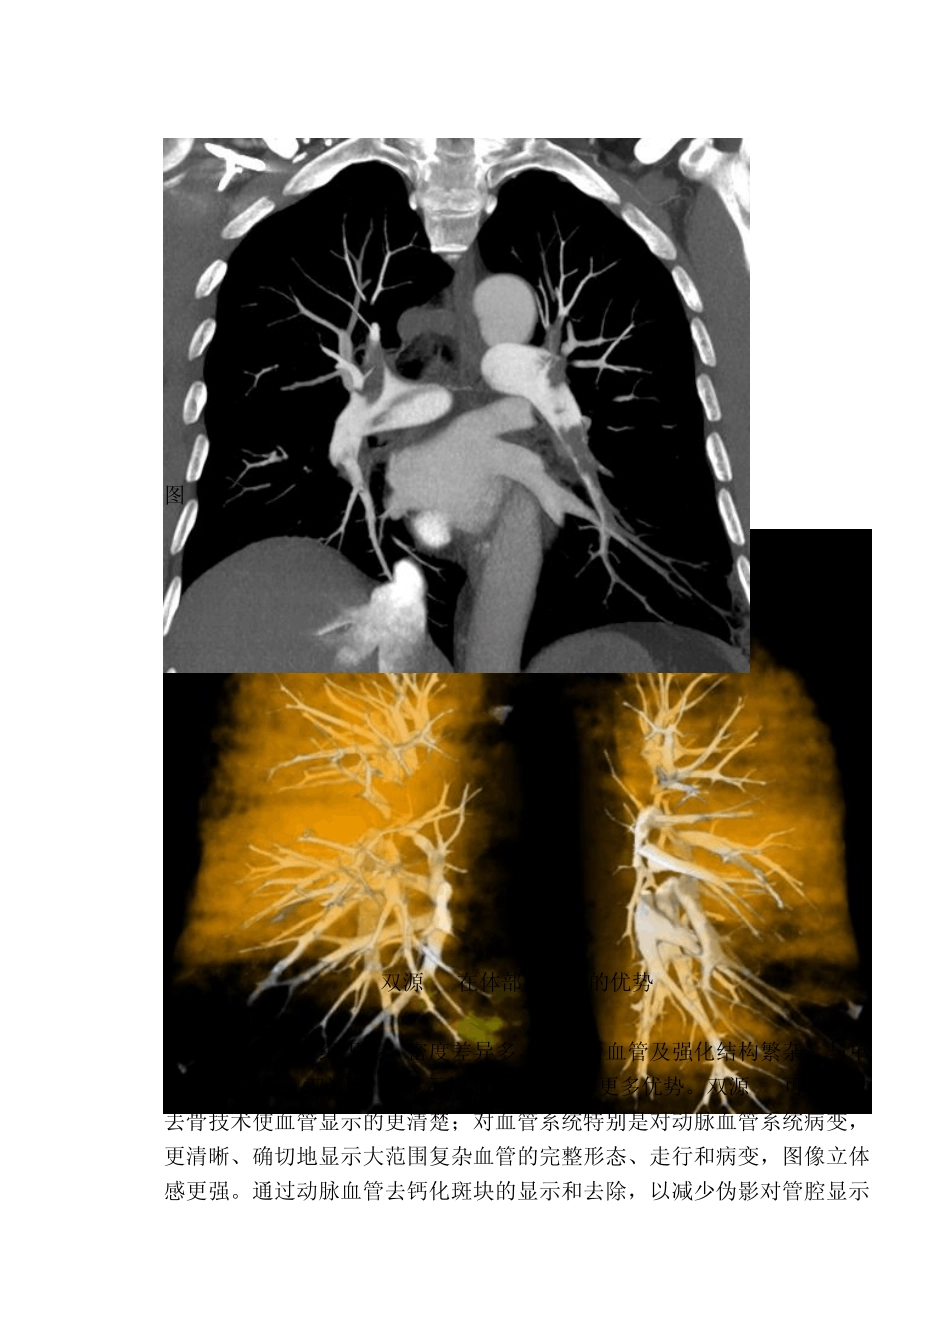

双源 CT应用简介: 头颅 CTA 蛛网膜下腔出血及脑出血是常见的急症,它们的发病率较高,明确发病的原因是治疗的关键,动脉瘤破裂出血是蛛网膜下腔出血的主要原因,超过 95%的蛛网膜下腔出血的病人都是因为脑动脉瘤破裂引起的,而脑血管畸形则是中青年人脑出血的主要原因。头颅 CTA(血管造影)是诊断颅内动脉瘤和脑血管畸形的最主要方法,双源 CT扫描时血管和骨质的直接减影(去骨功能)是它的技术亮点之一,特别是在头颅 CTA方面更是单源 CT无可比拟的。它可以根据碘含量的特殊算法,更加清晰地显示脑血管,避免了常规血管成像去骨过程中常常造成颈内动脉颅底段显示欠佳的缺陷,大大减少手工操作后处理的时间,利用双源 CT的独特的血管成像原理重建出来的脑血管有着更清晰、更直观等优点,对明确诊断起了很大的作用。 图 1 图2 肺栓塞 急性肺栓塞是一种常见的血管急症,双源CT通过患者一次屏气快速完成扫描,结合轴位及三维重建图像可进行明确诊断,并可同时排除主动脉夹层或急性心肌缺血造成的不典型胸痛。通过血管内造影剂的充盈情况,可以观察血管内栓子形态、位置及造成局部管腔狭窄程度。从三维角度显示肺动脉主干,双侧肺动脉和分支血管的病变形态及血管狭窄程度。能直观显示肺灌注缺损区域。对急性肺栓塞的诊断及溶栓治疗后复查具有重要意义,为临床治疗提供了重要信息。 图3 图4 双源CT在体部CTA中的优势 体部结构复杂,组织多、密度差异多,增强后血管及强化结构繁杂,与单源CT相比较,双源CT在显示体部结构上具有更多优势。双源CT可以通过去骨技术使血管显示的更清楚;对血管系统特别是对动脉血管系统病变,更清晰、确切地显示大范围复杂血管的完整形态、走行和病变,图像立体感更强。通过动脉血管去钙化斑块的显示和去除,以减少伪影对管腔显示的影响。通过对粥样硬化斑块的分析,较准确地分辨软斑块、混合斑块和钙化斑块,以进一步判断其稳定性,为临床选择治疗方式提供依据。 图 5颈部 CTA 图 6颈部 CTA 图 7颈部 CTA 图8布加综合症 图9布加综合症 双源CT可以区分尿路结石 双源CT能量成像以两个不同能量X射线源、不同电压值对同一解剖结构在一次扫描时采集到两组数据。改变了以往只能通过 CT值来做密度分辨率对比的局面。可用于标识、区分成像组织,以及病变定性研究。如结石成分分析等。 结石可以是多种成分的,如尿酸盐结石,草酸钙结石,三磷酸盐结石,胱氨酸结石等。双源CT能量分析能对结石成分进...